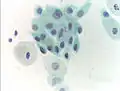

![]() High-grade squamous intraepithelial lesion | |

Micrograph of a normal pap smear